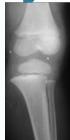

Injury films

Case Example: 12-year-old male, Salter-Harris Type II